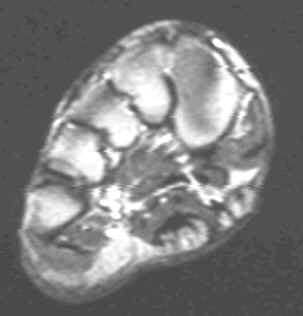

Characterized by nodular or poorly defined aggregates of mature to somewhat immature fibroblasts dispersed throughout dense collagen, causing irregular or nodular subcutaneous thickening of the plantar fascia. On MR, this appears as a nodular thickening of the plantar aponeurosis, which has low to intermediate signal intensity on both T1 and T2W images. Central increased signal intensity may be present.

62-year-old male with nodular thickening of the plantar fascia. This has intermediate signal on T1W and hyperintense signal on T2, proton density and Stir weighted images. These are atypical signal characteristics of plantar fibromatosis.